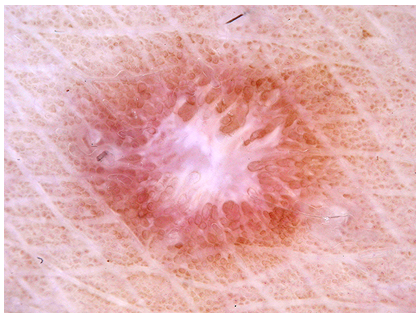

The ISIC 2018 dataset is provided by the Skin Lesion Analysis Toward Melanoma Detection 2018 challenge [2], for prediction of seven disease categories with dermoscopic images, including: melanoma (MEL), melanocytic nevus (NV), basal cell carcinoma (BCC), actinic keratosis/Bowen’s disease (AKIEC), benign keratosis (BKL), dermatofibroma (DF), and vascular lesion (VASC) (example images are provided in Fig. 2). It comprises 10,015 dermoscopic images, including 1,113 MEL, 6,705 NV, 514 BCC, 327 AKIEC, 1,099 BKL, 115 DF, and 142 VASC images. We randomly split the data into a training and a validation set (80:20 split) while keeping the original interclass ratios, and report evaluation results on the validation set. The employed evaluation metrics include accuracy, Cohen’s kappa coefficient [3], and unweighed means of F1 score and Jaccard similarity coefficient.

MEL

NV

BCC

AKIEC

BKL

DF

VASC